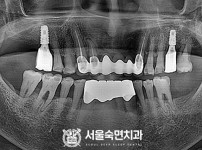

임플란트-전후사진2

치과를-선택할-때-꼭-확인하세요-서울숙면치과-임플란트-전후사진